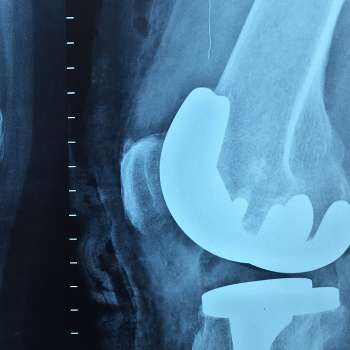

무릎에 물이차는 원인 1. 관절염 (Arthritis)

- 관절염은 무릎 관절에서 발생하는 염증으로, 주로 류머티즘 관절염, 골관절염, 혹은 강직성 척추염과 같은 다양한 형태가 있습니다. 무릎 관절 내의 연조직을 공격하여 염증 반응을 유발하며, 이로 인해 통증과 함께 물이 찰 수 있는 상황이 발생할 수 있습니다.

무릎에 물이차는 원인 3. 퇴행성 관절 질환

- 퇴행성 관절 질환은 무릎 관절의 연골이 시간이 지남에 따라 닳아지고 손상되는 상태를 포함합니다. 주로 고령자에서 발생하며, 연골의 감소로 인해 무릎 관절 내에 물이 찰 수 있는 조건이 형성됩니다. 이는 관절을 보호하는 기능을 약화시키고 물이 축적되게 합니다.

무릎에 물이차는 원인 8. 류마티스성 관절염 (Rheumatoid Arthritis)

- 무릎 관절을 포함한 여러 관절을 영향을 주는 면역 체계의 과도한 반응으로 인해 발생하는 염증성 관절 질환입니다. 무릎에 염증이 발생하면 관절 주위의 혈관이 확장되어 독소와 유체가 축적될 수 있습니다. 이로 인해 물이 차고 부음이 발생하며, 무릎의 움직임에 제약이 생길 수 있습니다. 또한, 무릎 통증과 함께 조인트 디폼리티(관절 형태의 변형)가 나타날 수 있습니다.